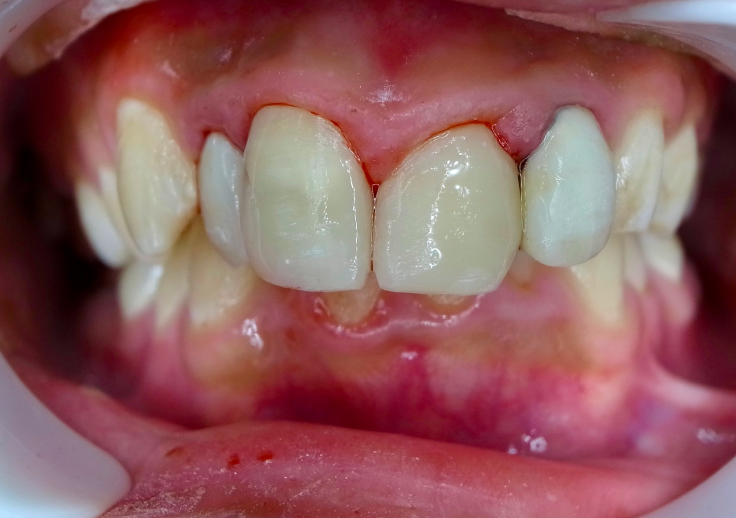

Before

After